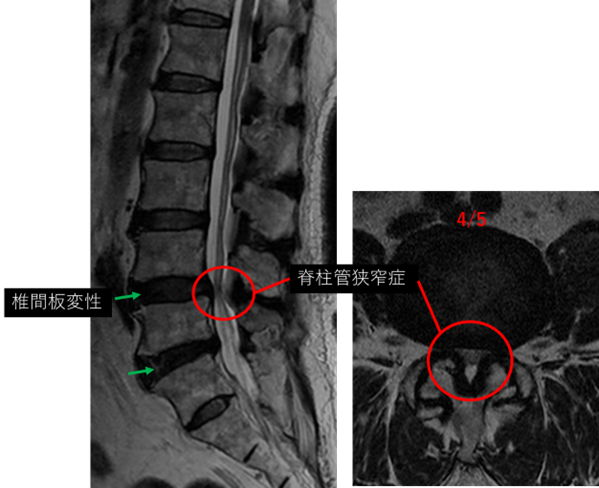

L1/2: なし

L2/3: なし

L3/4: なし

L4/5: 椎間板変性、椎間板膨隆、黄色靭帯肥厚、脊柱管狭窄

L5/S: 椎間板変性、椎間板膨隆

以上の事が画像上認められます。

L4/5、5/S に

椎間板変性、椎間板膨隆、黄色靭帯肥厚、脊柱管狭窄 を認め、主症状の原因の可能性が高い。